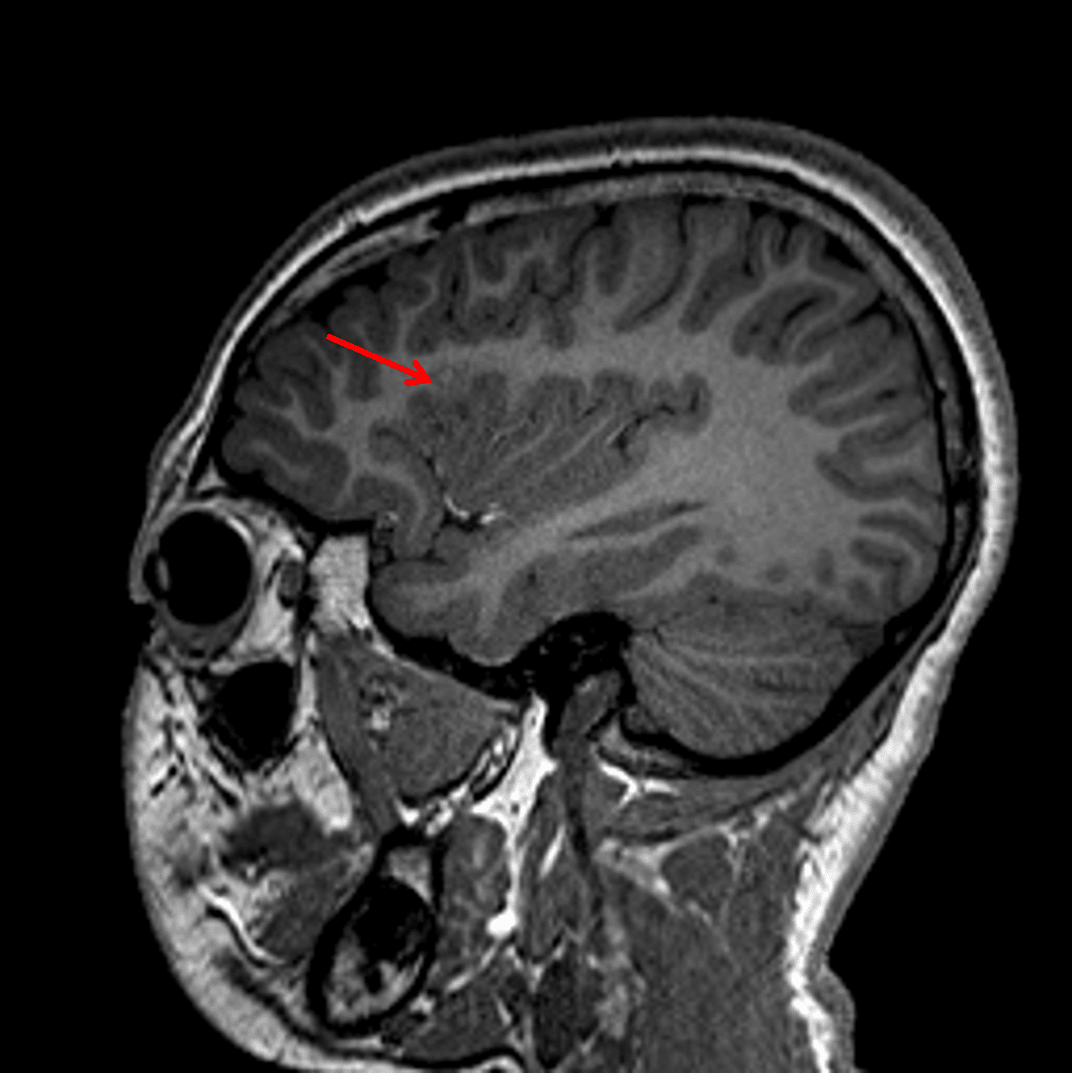

- Associated blurring of the gray-white interface

Associated blurring of the gray-white interface on T1 (red arrow).